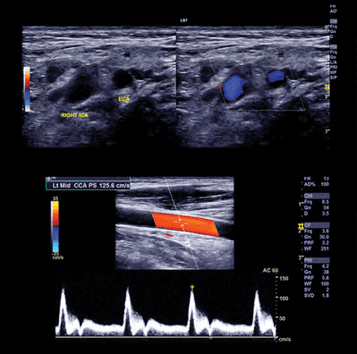

- Carotid Duplex Ultrasonography — Mary Mingzhu Yan, RVT

- Carotid Arterial Case Presentations — Drena Root, RVT